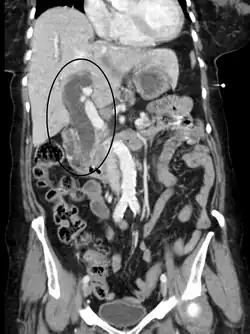

Ces examens sont distingués en non-invasifs et invasifs. Les examens non-invasifs sont utilisés en première intention, dans le but d'évaluer une obstruction des voies biliaires, l'état du foie et du pancréas, l'état vasculaire… Il s'agit de :

- l'échographie abdominale avec doppler.

- IRM abdominale et biliopancréatique.

- Tomodensitométrie abdomino-pelvienne avec injection.

Plus risqués, et selon des indications particulières (nécessité de ponction ou de biopsie ou à visée thérapeutique) sont des examens invasifs tels que l'échoendoscopie et différents types de cholangiographie (en)[12],[14].